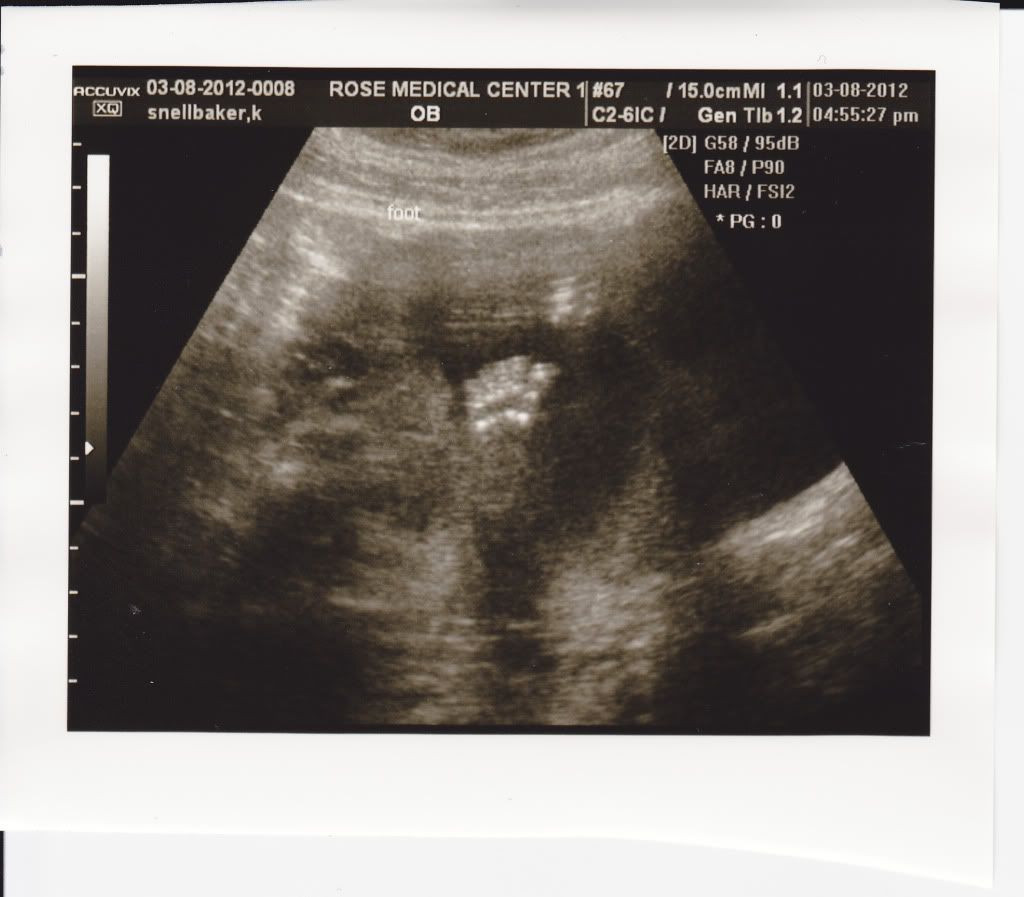

This is your little foot!